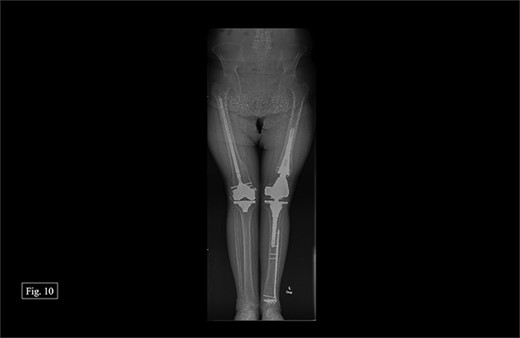

During her most recent visit in February 2024, 17 months post-op on the right, bilateral AP, right & left lateral, right & left AP, and full leg-length X-rays were taken. When looking at the right AP and lateral imaging, she had findings of progressive bone healing, maintained surgical alignment, and all hardware was intact (Fig. 8). Further, when looking at the bilateral AP and full leg length imaging, she had maintained hip alignment, equal leg length, and no changes in valgus or varus leg alignment (Figs 9 and 10). The patient reported a resting right knee pain of 1/10 and an ambulatory right knee pain of 2/10 with a full ROM. She was instructed to continue at-home physical therapy and NSAIDs as needed for pain and to return to the clinic in 6 months for further evaluation.